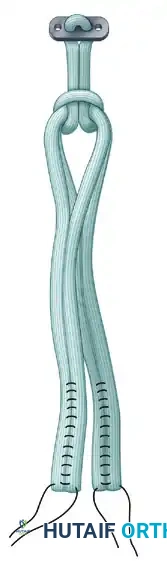

- EndoButton Selection: Measure the total width of the lateral femoral condyle. Select an appropriate EndoButton continuous loop (Acufex-Smith Nephew, Memphis, TN)—usually 2 to 3 cm—ensuring that approximately 2 cm of the quadruple hamstring graft will remain docked within the lateral femoral condyle.

- Graft Loading: Pass the EndoButton continuous loop around the middle of the doubled tendons, looping it inside itself to secure the tendons proximally.

- Femoral Fixation: Pull the EndoButton and tendons up through the tibia and out the femoral hole. Because the transepiphyseal femoral hole is larger than the standard EndoButton, an EndoButton washer (Smith & Nephew, Memphis, TN) that is 3 to 4 mm larger than the femoral hole must be placed over the EndoButton. Apply distal tension to the graft, pulling the EndoButton and washer flush against the lateral femoral condyle cortex.